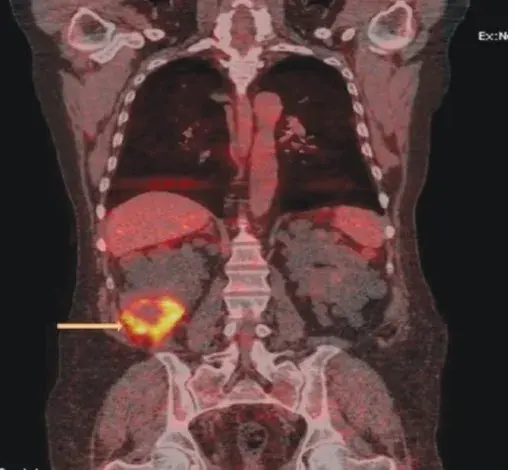

Caso muito ilustrativo publicado no Kidney 360 (link) Paciente do sexo feminino com 43 anos e com antecedente de nefrite lúpica (NL) proliferativa há 13 anos. A paciente apresentava histórico de acometimento grave da doença, com múltiplos tratamentos com infusões de metilprednisona e ciclofosfamida devido ao acometimento do sistema nervoso central (SNC) e da NL.